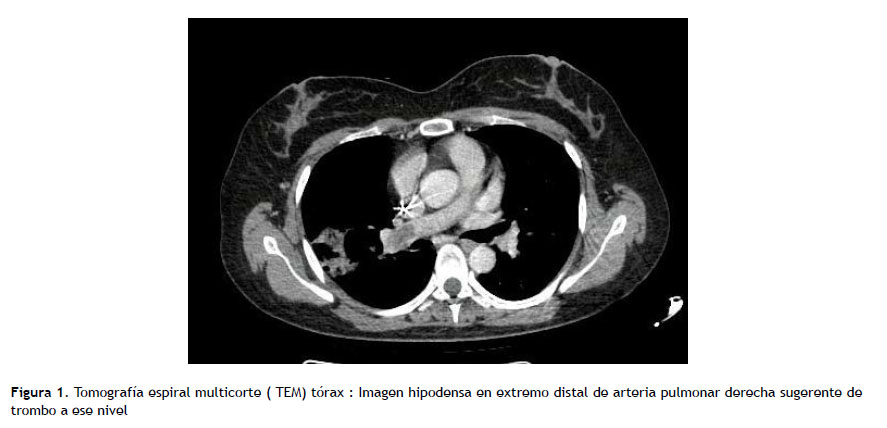

Paciente mujer de 36 años, con diagnóstico de vasculitis leucocitoclástica y uso de morfina como terapia para el dolor crónico, administrada por PAC desde hace un año, sin antecedente de episodios previos de infección del catéter. Ingresa por emergencia por 10 días de fiebre intermitente, tos y dolor torácico, con evidencia tomográfica de infiltrado pulmonar en base de hemitórax derecho y se decidió iniciar cobertura antibiótica de amplio espectro con imipenem y vancomicina. Al examen físico no se evidenció signos inflamatorios en zona externa del catéter. En el quinto día de hospitalización se reportó aislamiento de C. parapsilosis, en un set de hemocultivos periféricos tomados al ingreso, con susceptibilidad a fluconazol (CIM ≤2µg/mL), caspofungina (CIM ≤2µg/mL), anidulafungina (CIM ≤2µg/mL) y voriconazol (CIM ≤0,12µg/ mL), según antifungigrama (método automatizado Vitek2- puntos de corte aprobados CLSI/M27-S4-2012). La paciente refirió exposición previa a azoles. Inició tratamiento con caspofungina 70mg EV dosis de carga y luego 50mg EV c/24 horas por 5 días; y con hemocultivos posteriores negativos a las 48 horas más caída de la fiebre, se decide continuar tratamiento con fluconazol 800 mg/día EV hasta completar 14 días de tratamiento antifúngico. El examen de fondo de ojo fue normal, y por la aparente evolución favorable no se realizó estudio ecocardiográfico. Sin embargo, a los dos días de haber concluido la terapia antifúngica cursó con deterioro clínico evidenciándose en nueva tomografía de tórax imagen sugestiva de trombo en el extremo distal de la arteria pulmonar derecha con extensión a ramas interlobares (Figura 1), lo cual coincide con nuevo cuadro febril y dolor torácico, por lo que se realizó inmediatamente una ecocardiografía transesofágica (ETE), donde se objetivó en el PAC múltiples vegetaciones > 20 mm en su trayecto, siendo la mayor de 4 cm (Figura 2).